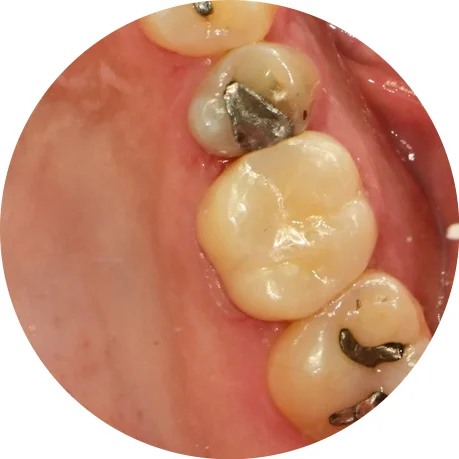

4번째 신경관이 보여 길을 찾아보았습니다. 같이 주행하는 것처럼 보이시나요?^^

약간 다른 각도로 촬영해 보니 두 개의 신경관이 각기 다른 길로 주행하고 있습니다. 이런 치아에서 다른 하나의 신경관을 찾지 못했다면 신경치료 후 통증의 원인이 될 수 있습니다.

근관충전 결과

사진에 표기된 두 개의 신경관이 하나의 뿌리에서 각기 주행하는 다른 신경관입니다! 이렇듯 치아 내부의 신경관은 복잡하고 변이가 많아 신경치료를 모두가 어려워하는 실정입니다^^

신경치료가 완료된 후 촬영한 사진에서 모든 신경관이 가득 채워진 것 같으면 잘 된 신경치료로 볼 수 있습니다!